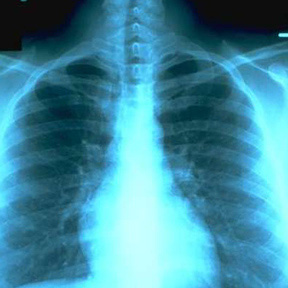

- Plain x-rays